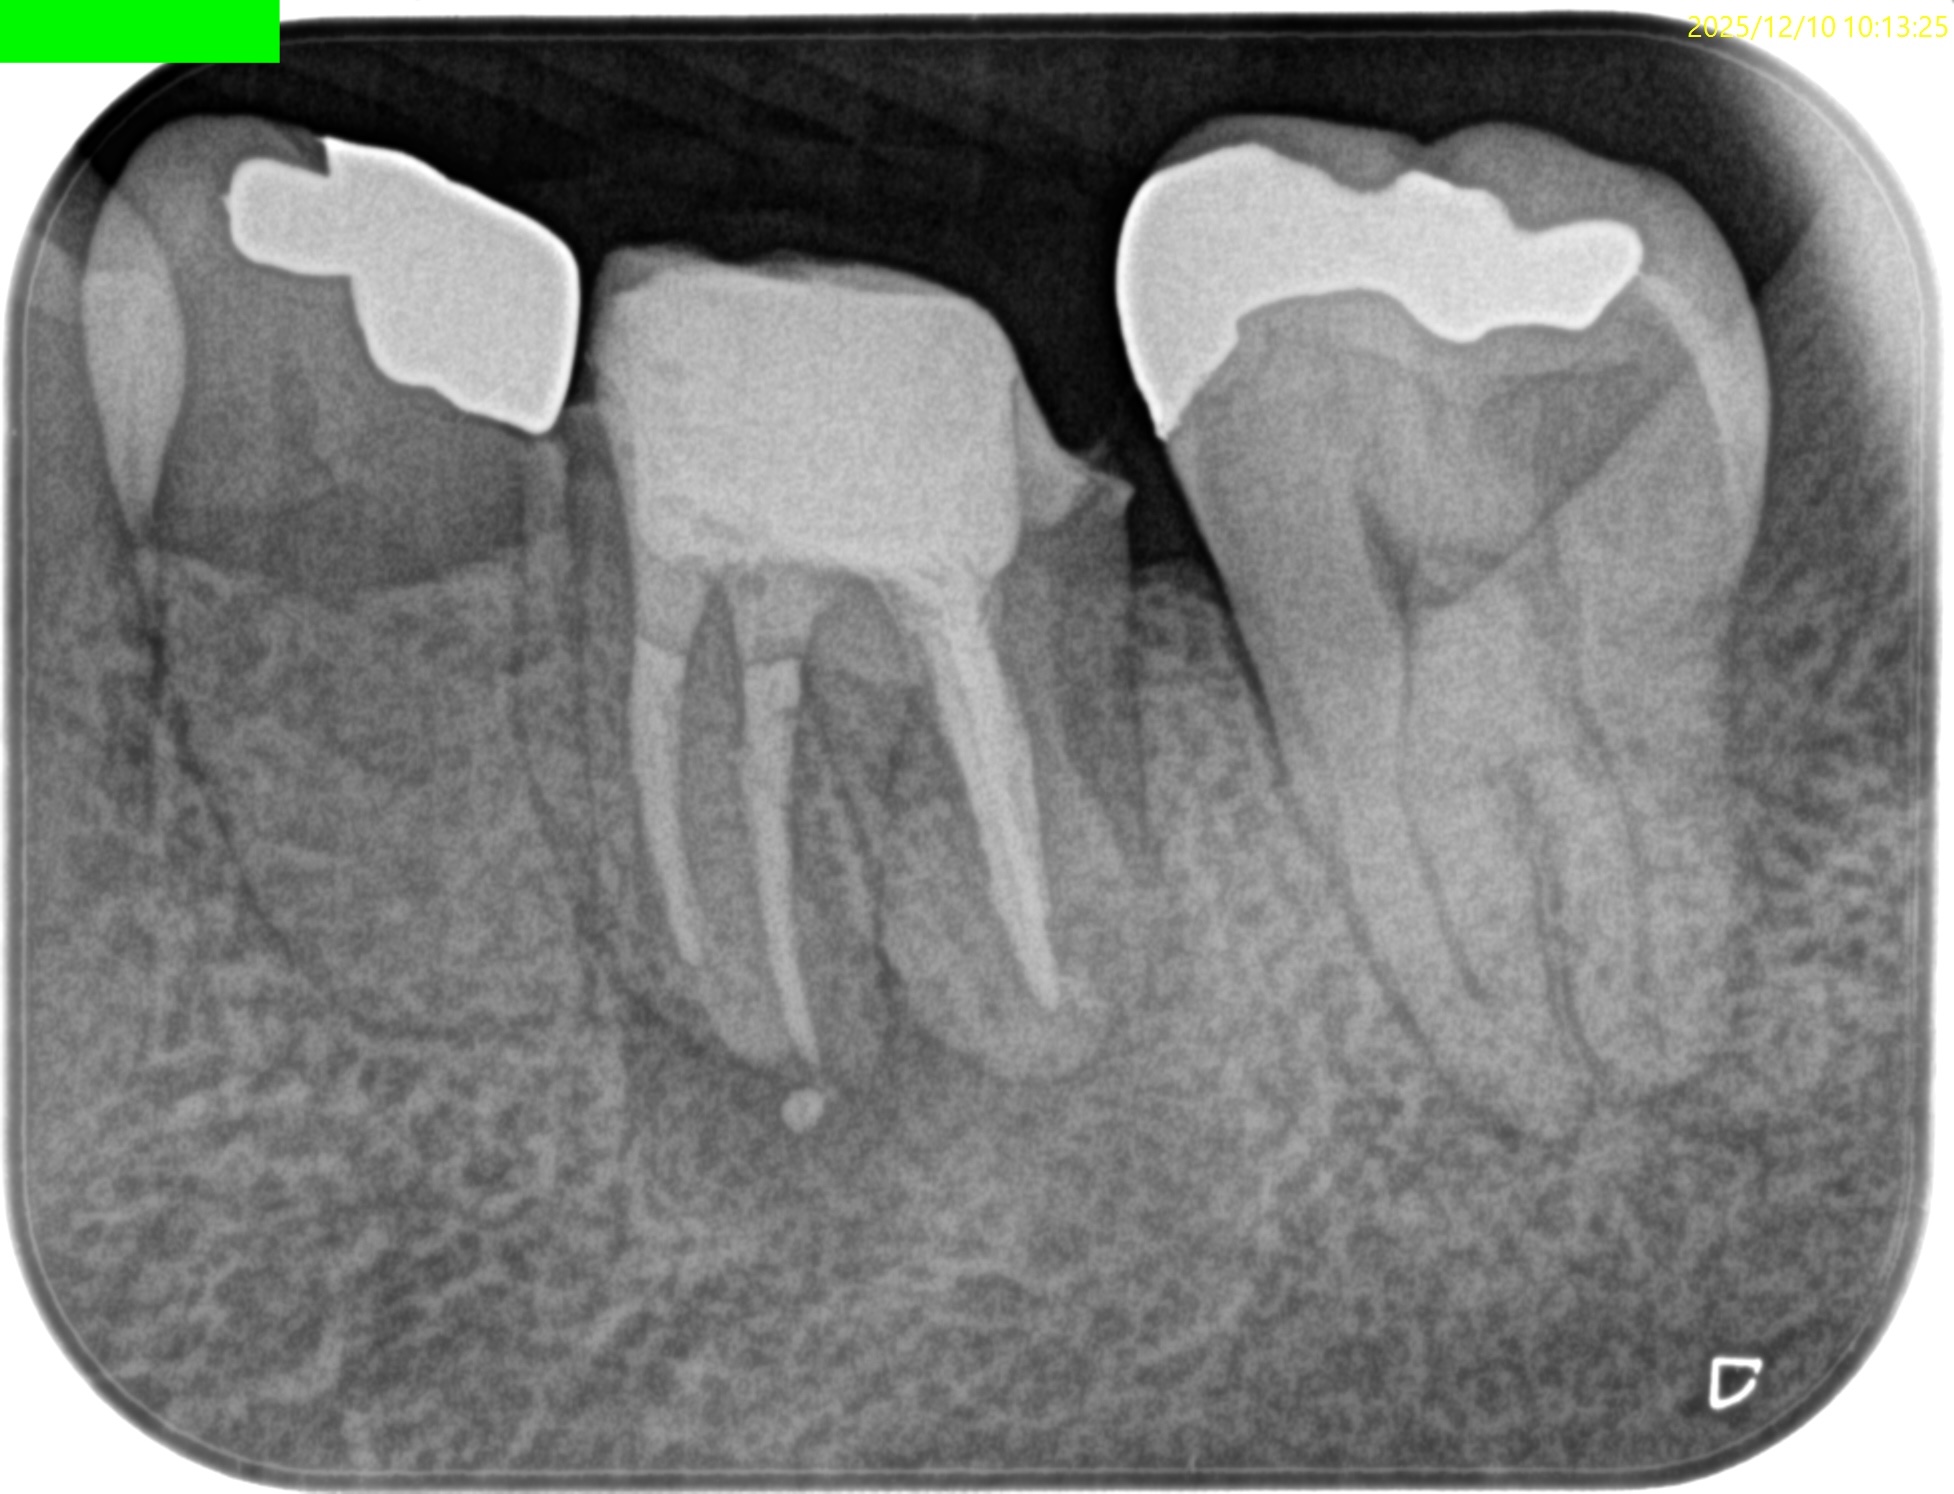

PA(2025.12.10)

CBCT(2025.12.10)

ML

MB

D